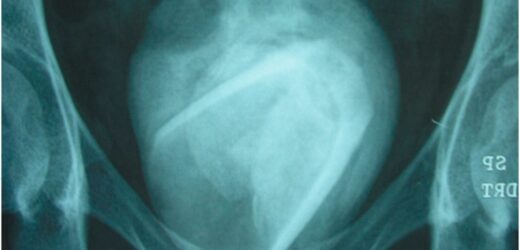

But doctors were left stunned when scans found an 8cm-wide bladder stone, with a glass inside it.

Her case was published in a medical journal, including the astonishing scan and an image of the glass and bladder stone.

Bladder stones are usually too small to be seen by the naked eye, or a few cms wide – this patient's was 8cm.

In this case, doctors performed a cystolithotomy to remove the bladder stone.

They then cracked it open to expose the – still in tact – glass, that had been in her body for years.